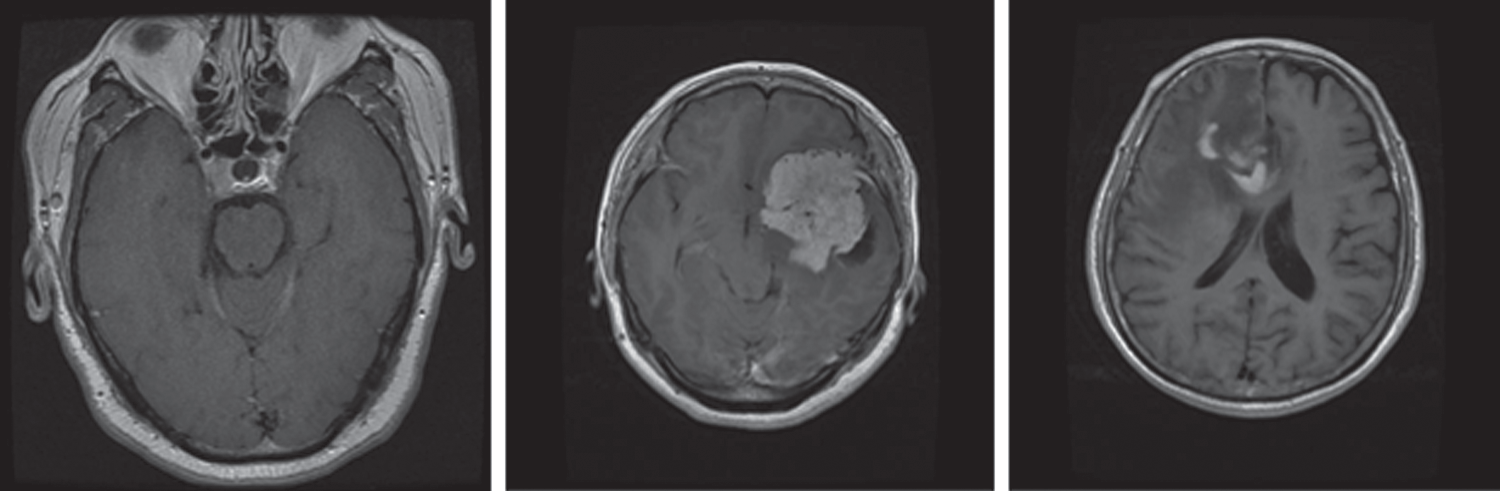

An MRI dataset containing 3,064 brain MRI slices was used for training and testing of the proposed models. This dataset was obtained from 233 different patients. The dataset comprises three different and prominent classes of brain tumors: Meningioma, glioma, and pituitary (Fig. 1). Specifically, it has 930 images of pituitary tumors, 708 images of glioma, and 1426 images of glioma tumors. The brain tumor dataset was provided in matfile and was first converted into a PNG image format for processing. All deep learning models require a dataset in the batch format. Therefore, this dataset was converted into a tensor format from the PNG image files with different batch sizes for use in the proposed models. Min–max normalization was used within the range of 0–1 for the pixel intensity.

Figure 1: MRI sample images of different brain tumors